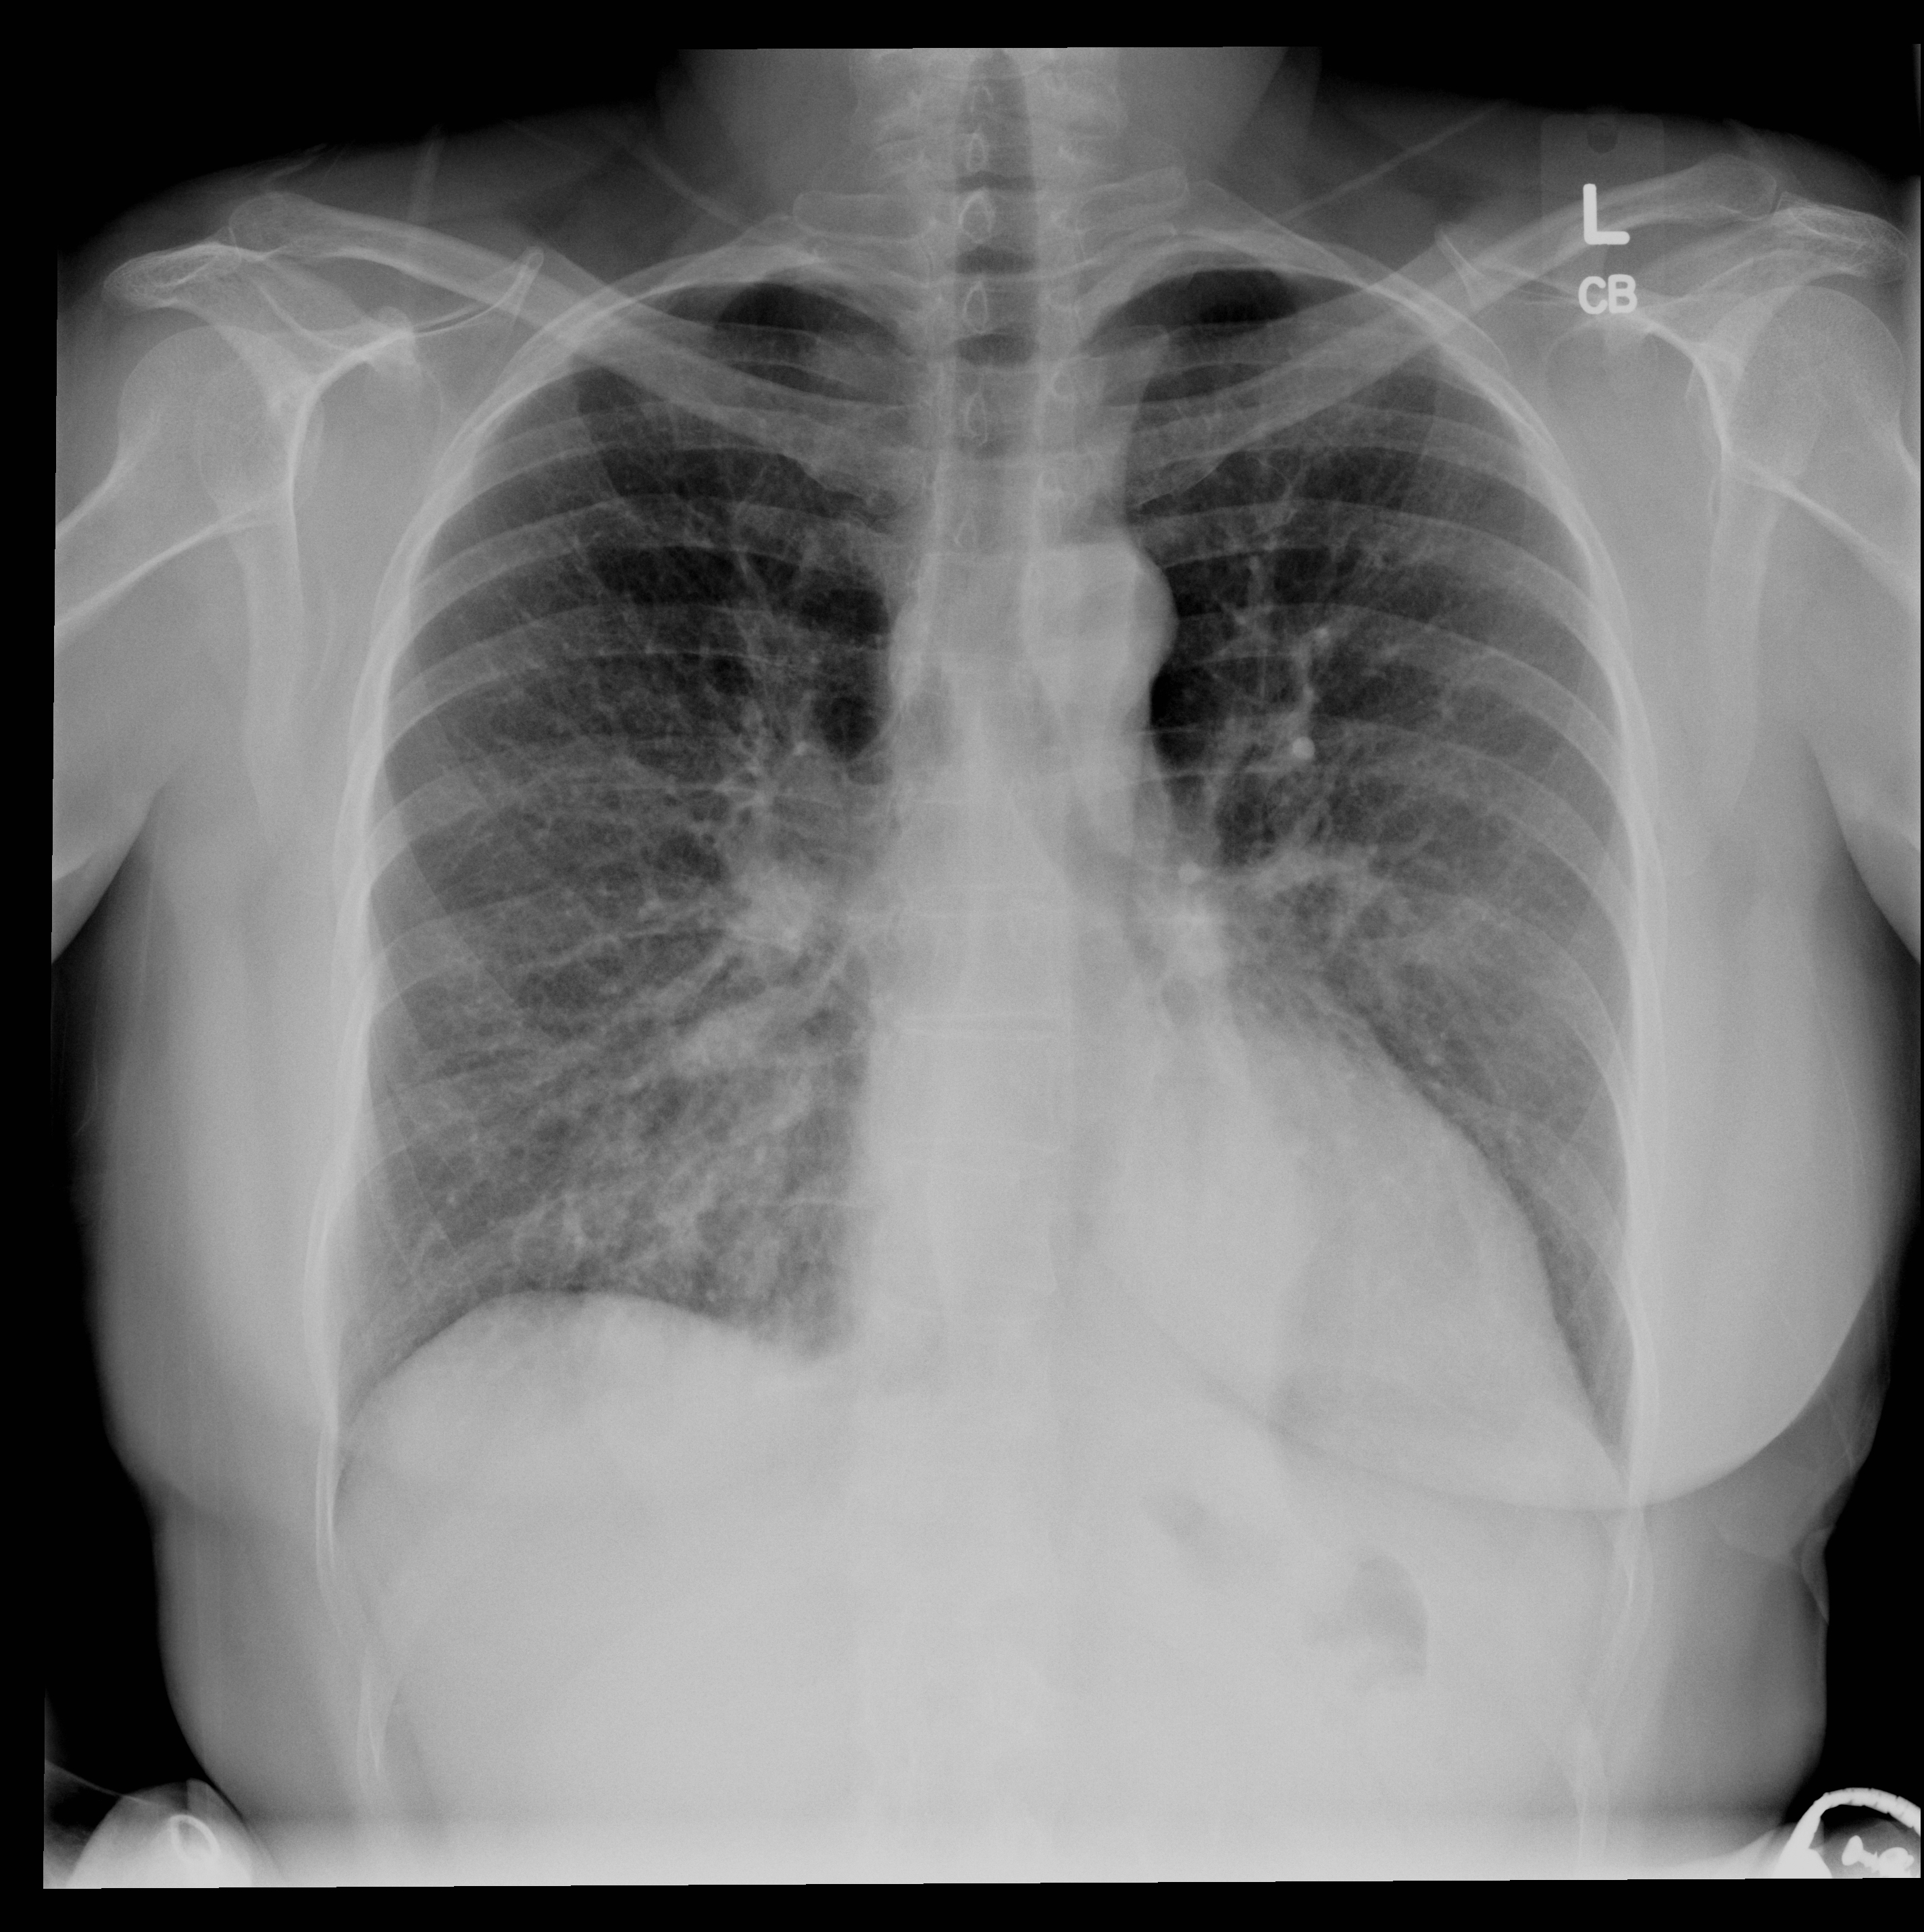

| 21 |

Abnormal lt ll collapse |

Abnormal Left lower lobe collapse |

Correct |